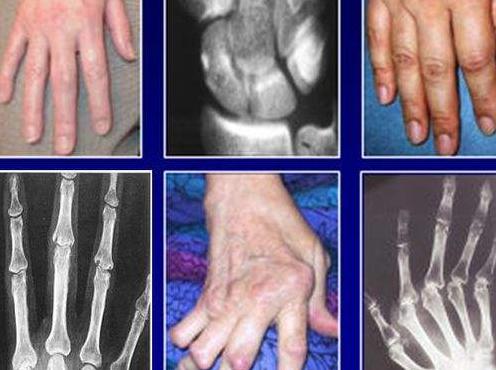

類風濕性關節(jié)炎具有隱匿性高、難確診、受損不可逆和致殘率高等特點。它可以發(fā)病于身體的任何一個關節(jié),常發(fā)病于指、掌、腕部小關節(jié)。

據調查研究表明,隱匿型類風濕性關節(jié)炎患者占類風濕關節(jié)炎病人總數的60-70%。緩慢起病,常于數周或數月內逐漸起病,表現為掌指關節(jié)和腕關節(jié)的疼痛、腫脹和僵硬,可伴全身不適和乏力、低熱、食欲不振、體重下降等。

2、經過數周或數月后出現關節(jié)疼痛、腫脹,往往從一個或幾個關節(jié)受累,常首先累及大關節(jié),在一段時間內病變局限于該關節(jié),逐漸發(fā)展到數個、十幾個或數十個關節(jié)受累,終可擴散到腕、指、踝、趾等多個關節(jié),呈兩則肢體關節(jié)的對稱性分布。